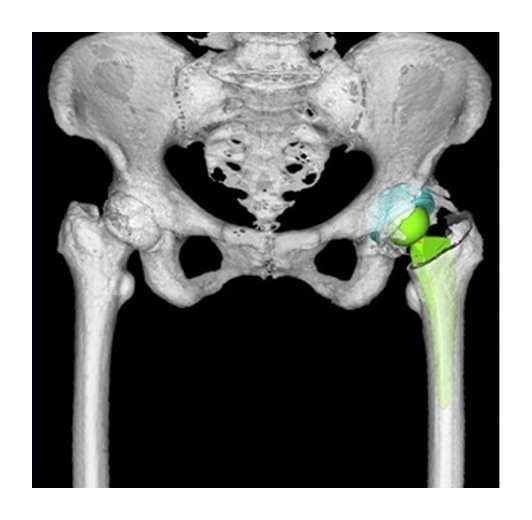

また、手術は患者様の体にできるだけ負担をかけない低侵襲(MIS)アプローチを採用しています。術前3Dテンプレート計画や簡易ナビゲーションシステムなどの先端技術を活用し、脚長差や可動域のバランスにも細心の注意を払います。